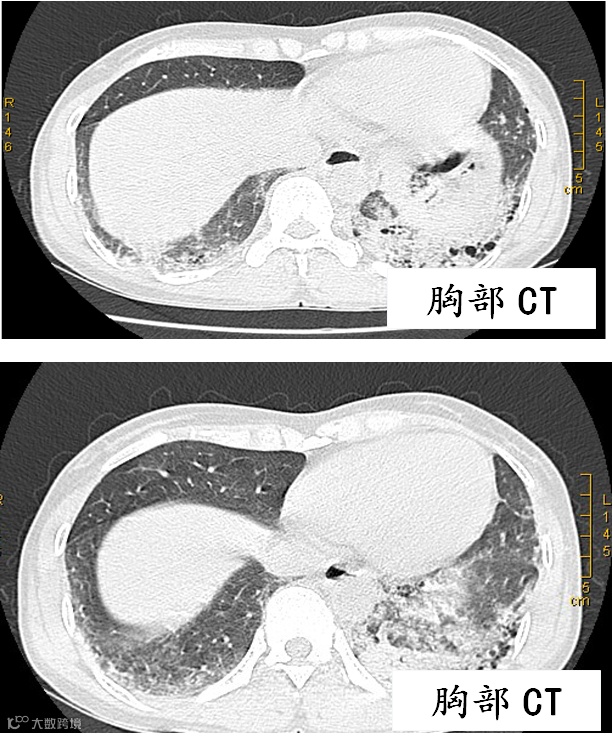

于是,胡大夫将自己心中的疑惑立即汇报给了呼吸内科主任关巍教授。关主任带领医师们到何大姐床旁进行查房,再次详细询问病史和进行体格检查,何大姐的肺底部可以听到明显的爆裂音,在吸气末的时候听得特别清楚。关主任查房后,基本可以肯定患者存在风湿免疫系统疾病,建议她尽快完善胸部CT、风湿九项、肺功能等检查。何大姐按医生的考虑做了一系列的检查,包括生化常规、风湿九项、胸部CT、肺功能全套等等检查。胸部CT提示双下肺间质性肺炎改变,肺功能检查提示中度限制性肺通气功能障碍,弥散功能下降。